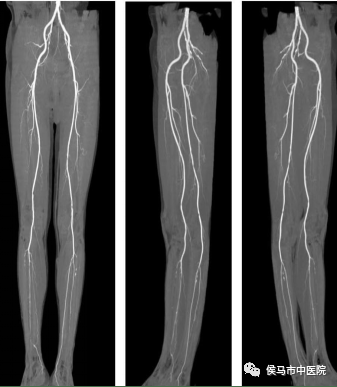

5、双下肢动脉CTA

通过CTA可以明确下肢动脉形态、有无管腔狭窄、有无闭塞、动脉硬化程度、有无动脉瘤样扩张等情况。是检查下肢动脉疾病的一项重要无创检查手段。